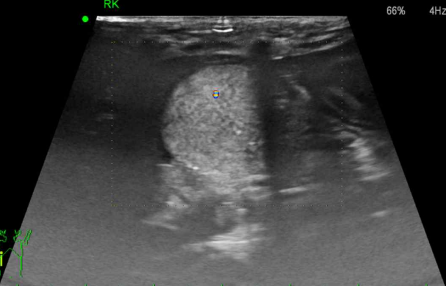

• 초음파 검사

피질, 수질 경계가 없음, hyperechoic